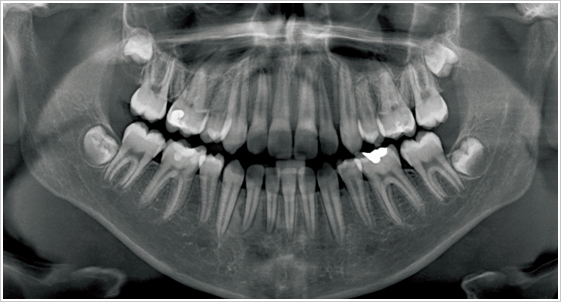

牙科專用的電腦斷層(Computed Tomography 簡稱CT)和一般的醫療電腦斷層的不同在於傳統牙科X光攝影所得的平面影像受到組織重疊的影響,無法觀察到內部的實際狀況,醫師常常因此造成誤判,為解決此問題,就需要牙科專用的3D電腦斷層攝影;若與傳統醫療電腦斷層相比較,牙科3D電腦斷層攝影有很多優點,如輻射劑量只有一般電腦斷層的1/50;採站姿或坐姿攝影,方便行動不便的患者;切片厚度一般醫療電腦斷層是 2.0 公厘,牙科3D電腦斷層則只有0.1公厘,解析度之高,比起一般醫療電腦斷層,影像當然來得細緻和精確。

美國口腔顎面放射學會-AAOMR (The American Academy of Oral and Maxillofacial Radiology)2001 年研究文獻指出,從事植牙手術前醫師除了透過全口X光影像、根尖片影像觀察近遠心距離外,應再拍攝電腦斷層(CT)影像,藉由切面影像(Cross-sectional view)以事先評估出齒槽骨寬度、舌頰側的距離、骨質及組織的密度,才能提昇植牙手術的安全性。